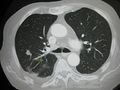

صورة أشعة مقطعية لانبثاث في الرئة

سرطان منتشر في الرئتين